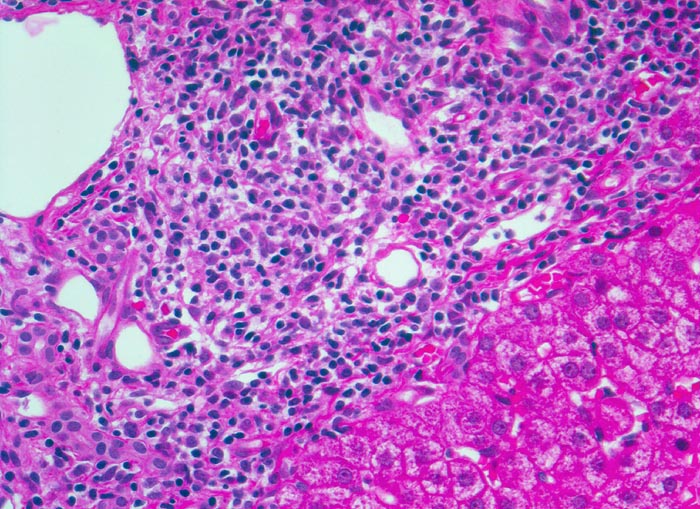

PathoPic – image database / PathoPic ID 4964 - chronische Hepatitis C mit geringgradiger Aktivität

chronische Hepatitis C mit geringgradiger Aktivität

Links im Bild Portalfeld mit starker Vermehrung von Lymphozyten mit kleinen runden Kernen und Plasmazellen mit exzentrisch gelegenen Kernen und basophilem Zytoplasma mit perinukleärer Aufhellung.

Fibrose der Portalfelder mit portoportaler Septenbildung.

Intravenöser Drogenabusus vor 10 Jahren. Damals Infektion mit dem Hepatitis C Virus.